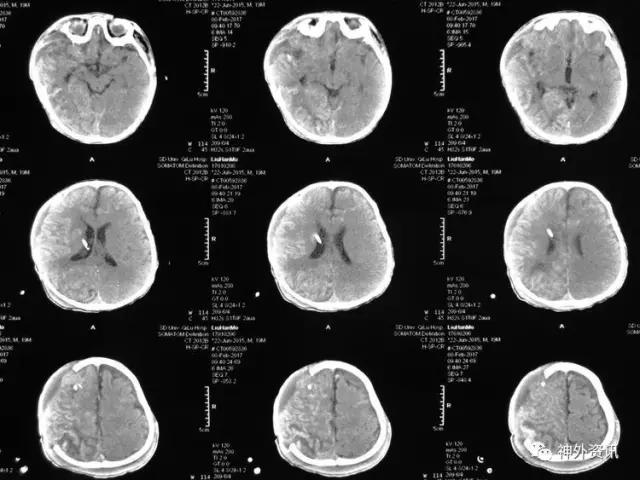

患儿刘**,男,19个月,2017.1.30 2pm不慎摔倒,意识障碍,刺痛不睁眼,不发音,刺痛肢体屈曲,急至当地医院,伤后1小时颅脑CT结果示右额颞顶枕急性硬膜下血肿,中线轻微左移:

3小时后转至我院急诊科,当时查体:刺痛不睁眼,不发音,刺痛右侧肢体屈曲,右侧瞳孔5mm,对光反应消失,左侧瞳孔0.3cm,对光反应迟钝,立即术前准备并复查CT,结果示右额颞顶枕硬膜下血肿,右侧大脑半球及左侧额叶弥漫性低密度,考虑缺血,中线左移明显,脑沟及环池显示不清:

术后移动CT结果示中线移位较术前减轻,顶枕部蛛网膜下腔出血:

2017.2.1:术后2天复查颅脑CT,结果示中线居中,右侧半球低密度并SAH,左侧半球未见明显异常,左侧脑沟可见显示,双肺少量炎症,不能放松警惕,继续同前治疗。

2017.2.4:术后5天复查颅脑CT,结果示中线居中,左侧半球及环池显示清晰,右侧半球脑沟显示欠清晰,脑组织低密度较前有所好转,继续同前治疗。已加用预消化肠内营养液及促进胃肠动力药物。

2017.2.6:术后7天,复查颅脑CT示情况较前进一步好转,逐步撤掉冰毯,缓慢自然复温。

2017.2.8:术后9天,复查颅脑及胸部CT,结果显示双侧脑沟脑回及环池显示清晰。颅压控制,拔除引流管探头,头部敷料稍加压包扎,此时已更替力月西为丙泊酚,停用呼吸机。